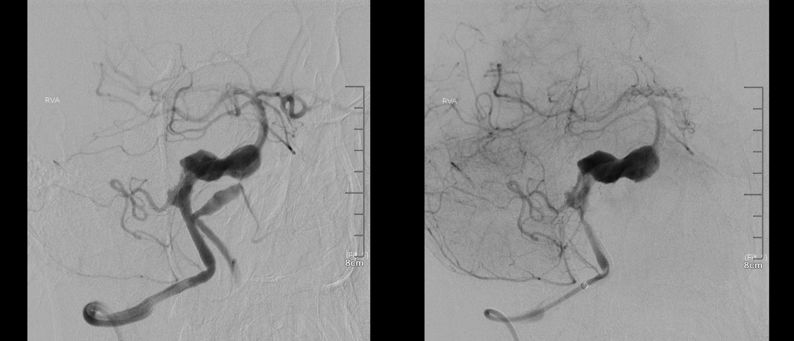

术前右椎动脉造影显示:基底动脉中下段巨大夹层动脉瘤存在,PED支架向下移位脱落至基底动脉下段。

术前右椎造影:

术前右椎动脉路途下显示PED 支架向下回缩,支架近心端回缩不明显。远心端至动脉瘤下。箭头所示为支架远端脱落至动脉瘤内的位置。